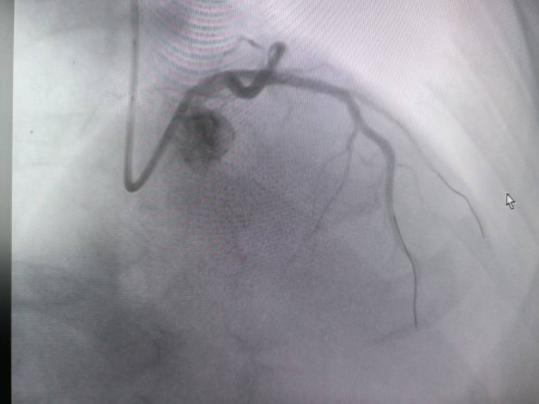

近年来,急性心梗发病呈现年轻化趋势,“80后”群体发病率逐年攀升。在过去的8天里,榆林市星元医院胸痛介入团队为4名“80后”急性心梗患者紧急开通心脏血管,挽救了4颗年轻而鲜活的心脏。其中,一名34岁男性患者突发胸痛2小时入院,心电图显示为广泛前壁ST段抬高型心肌梗死(STEMI)。医院迅速一键启动急诊胸痛绿色通道,30分钟内完成冠脉造影(CAG)及经皮冠状动脉介入治疗(PCI),成功开通右冠状动脉根部闭塞血管。术后患者胸痛即刻缓解,ST段显著回落,转危为安。

术前(冠脉开通前)

术后(冠脉开通后)